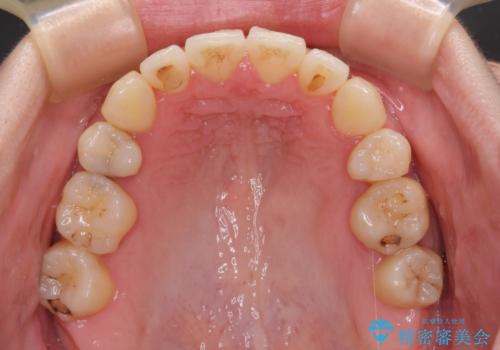

【モニター】上下の八重歯を治したい ワイヤー装置による矯正治療

- 上下前歯のデコボコを気にして来院された患者様です。

デコボコが強いため、非抜歯で矯正をすると出っ歯仕上がりとなるため、上下左右の第一小臼歯4本を抜歯することとしました。